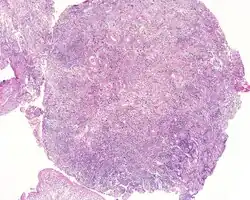

An intermediate magnification of a H&E stained biopsy from an otic polyp. | |

By microscopic exam, the polypoid appearance is maintained, showing a granulation-type tissue reaction with edematous stroma and a rich investment by capillaries. The surface of the polyp is covered by stratified squamous epithelium with a prominent granular cell layer. The tissue is filled with lymphocytes, plasma cells, mast cells, histiocytes, and eosinophils. It is not uncommon to see plasma cells with Russell bodies and Mott cell formation. Depending on length of symptoms, multinucleated giant cells and calcifications may be seen. Other disorders may be concurrently present, especially since this is a post infectious/inflammatory disorder, and these include a cholesterol granuloma, "tunnel clusters" (glandular epithelial inclusions below the surface epithelium), and cholesteatoma.[3][4][5]